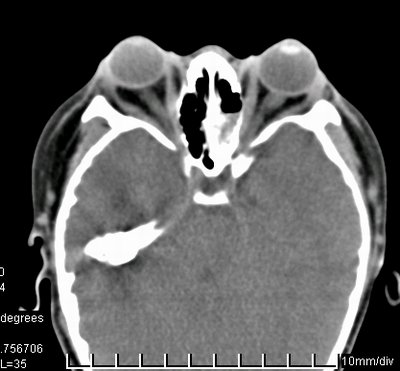

儿子的CT扫描

临床表现:突眼、眼眶浅、“鹦鹉鼻”、反咬颌、鼻咽狭窄、视神经孔窄、头颅畸形。可同时伴视神经萎缩、青光眼、白内障。